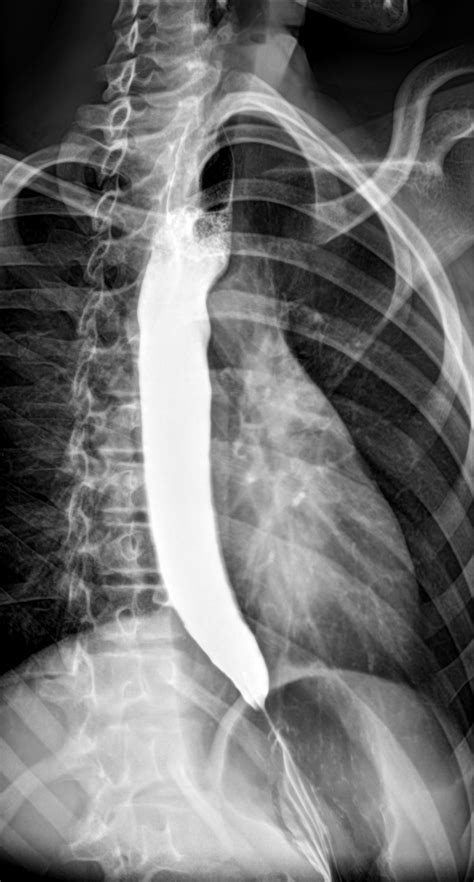

• Barium Swallow Test: This X-ray test involves swallowing a barium solution, which coats the esophagus and helps visualize any abnormalities.